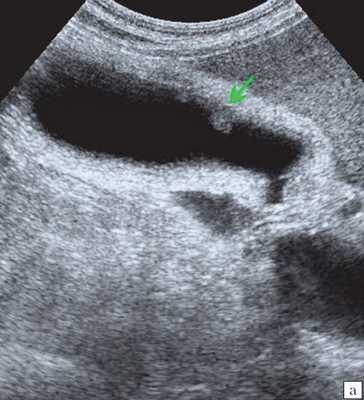

(Левый) На поперечном УЗ срезе через левую долю печени по ходу желчных протоков определяются множественные линейные эхогенные зоны, некоторые из них отбрасывают акустическую тень; такая картина отражает наличие газа в желчных протоках.

(Правый) На поперечном УЗ срезе через левую долю печени визуализируются линейные эхогенные очаги, отбрасывающие «грязную» акустическую тень; такие изменения вызваны наличием газа во внутрипеченочных желчных протоках.